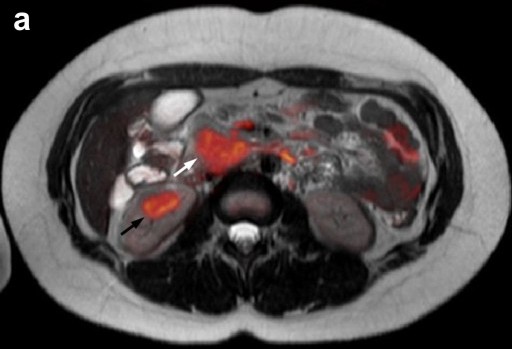

Contrast-enhanced MRI and diffusion-weighted imaging showed: a) an enlarged pancreas associated with highly restricted diffusion and delayed enhancement of the pancreas parenchyma as well as capsule-like peripheral enhancement in the late venous phase; b) main pancreatic duct strictures and chronic pancreatitis changes, suggesting possible autoimmune pancreatitis or a diffuse inflammatory process (Figure 1abc). Multiple mesenteric lymph nodes and two right renal mass-like lesions were also evidenced. 18F-fluorodeoxyglucose positron emission tomography/computed tomography (FDG-PET/CT) showed hypermetabolic activity within all lesions seen on MRI as well as less intense hyperactivity at the level of enlarged bilateral axillary lymph nodes (Figure 1d). These findings raised the hypothesis of lymphoma or tuberculosis. Endoscopic ultrasonography found a diffuse enlarged pancreatic gland and a 40 mm right renal mass. Fine needle aspiration (FNA) was performed both in the pancreas and in the kidney. Cytology showed non-specific inflammatory cells (Figure 2). IgG4-immunostaining was negative, serum IgG4 level was normal and anti-nuclear antibody was negative. Ultrasound-guided percutaneous renal biopsy was inconclusive, revealing a normal renal parenchyma. Cultures (containing a medium specific for mycobacteria and fungus) on FNA and percutaneous renal biopsy specimens were negative.

Figures 1. a. Fusion of axial MRI T2-weighted spin-echo and diffusion-weighted images showing high-intensity focal lesions in the pancreatic head (white arrow) and in the right kidney (black arrow). b. Late venous phase of contrast-enhanced axial MRI T1-weighted gradient-echo image showing a diffusely enhanced and enlarged pancreas with a high intensity capsule-like rim (arrows). c. MRCP image revealing a long segmental stricture (arrow) as well as dilatation and side branch ectasia of the main pancreatic duct. d. FDG-PET/CT showing multiple localizations of intense abnormal radiotracer uptake corresponding to the superior and inferior pole of the right kidney (open arrows), the head and body of the pancreas (closed arrows), and the axillary regions (arrowheads). |